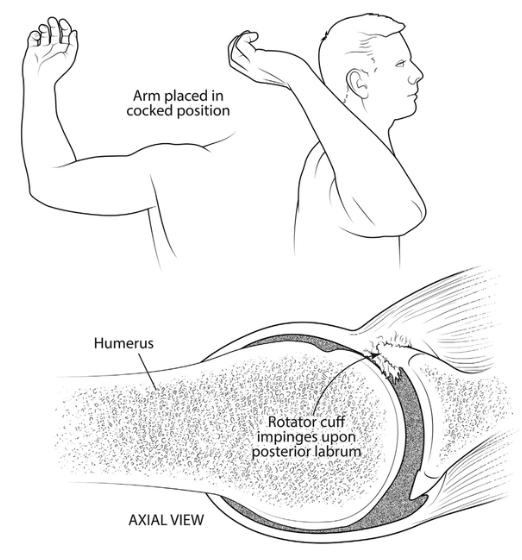

반면 어깨 뒤쪽은 상대적으로 관절와와 상완골두가 좁아지며 외회전, 수평외전 시 극상근, 극하근이 관절와순과 충돌이 많아지며 내적충돌을 일으킬 수 있습니다.(Internal impingement) 이 때 내적충돌은 전상방, 후상방에서 각각 일어날 수 있고, 주로 후상방에서 나타납니다.

참고로 내적충돌증후군은 어깨후방의 관절낭의 구축에 의해서 발생되며, 야구에서 투수가 공을 반복적으로 던지면서 생길 수 있습니다.